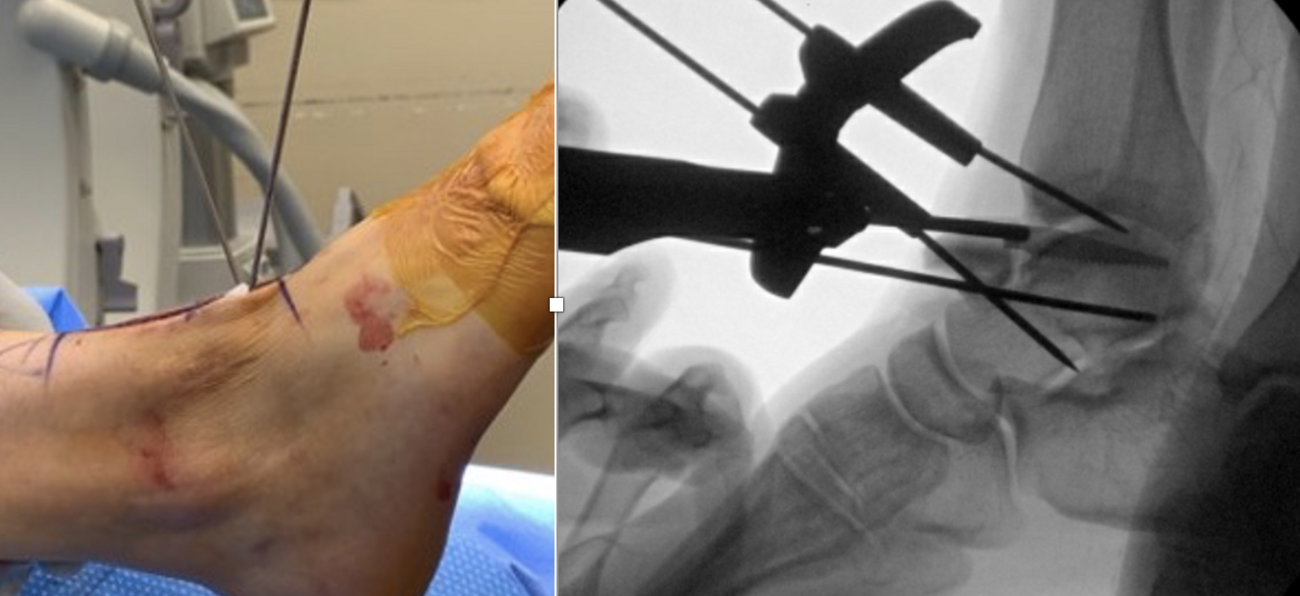

We presented the option of a patient-specific partial talar replacement with a plan to resect and replace the entire lateral shoulder. As part of the design process, the implant had custom cut guides that would sit on the talar neck, temporarily secured in place with smooth wires. This guide would then correlate with the final implants to ensure the appropriate amount of bone removal and allow more accurate bone resection. In addition, the design incorporated two stems in the final implant to add stability and fixation surface area. Three sizes of implant allowed intra-operative flexibility.

The incision was the typical anterior ankle approach. This would limit location of incisions for potential future issues or conversion to fusion or total implant. We then exposed the distal tibia and dorsal neck of the talus. Placing the prefabricated custom cut guide onto the neck of the talus, we then checked this under fluoroscopy to ensure placement, and the proper orientation and amount of lateral dome to be removed. We then pinned this guide in place with predetermined holes. A reciprocating blade limited blade excursion and minimized potential for injury to adjacent structures. After removal of the damaged piece of talus we placed the trials. The goal was to have the trial flush or even slightly recessed with regard to the adjacent cartilage. During weight bearing, the native cartilage will compress, so it is important to match the weight bearing level. If the implant is proud, then during weight bearing the cartilage will naturally compress, but the implant will not, potentially giving rise to issues with load bearing around the device.